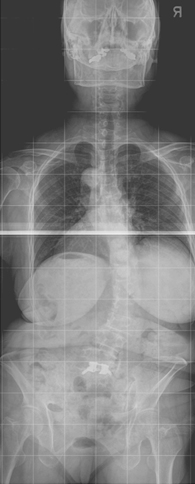

정상적으로 흉추는 기립 측면상에서 20~45도의 후만을 이루고 있습니다. 흉추 후만의 첨부는 제 7 흉추에 위치하며 흉추 후만각은 Cobb 방법상 제 4~12 흉추 사이의 각도를 측정합니다. 일반적인 방사선적 진단 기준으로 Schmorl 결절, 불규칙한 척추 종판, 추간판 간격의 협소를 동반한 적어도 3개 이상의 인접 척추의 5도 이상 설상변형이 제시됩니다. 척추 후만은 경직성으로 신전 시에도 변형이 남아 있으며 신전 시 측면 사진을 이용하여 만곡의 경직도를 가늠할 수 있습니다. 전후방 사진상 다양한 정도의 측만이 환자의 약 1/3에서 동반되어 있으며 척추 전방전위증이 동반된 경우도 있습니다. 동반된 척추 전방전위증은 대부분 협부형으로 대상성 요추 과전만으로 인한 추궁 협부의 긴장으로 설명됩니다. 변형의 유형에 따라 흉추형과 흉요추형으로 나눌 수 있으며 흉추형인 제 1형이 더 흔한 형으로 만곡의 첨부가 제 6~8 흉추 사이에 위치하며 흉추 후만증과 함께 경추와 요추의 과전만을 보이고, 흉요추형인 제 2형은 보다 드물며 만곡의 첨부가 제 10 흉추와 제 1 요추 사이에 위치한 흉요추부나 요추부의 후만증을 보입니다. 흉요추형이 보다 유연한 만곡을 가지며 늑골의 지지가 없으므로 만곡이 진행하는 경향을 보입니다.

주로 축성 골격을 침범하고, 천장관절을 침범하여 천장 관절염을 유발하며 통상 청소년기 후반에 증세의 발현이 시작되는 경우가 흔하고, 40세 이후의 증상 발현은 매우 드뭅니다. 남녀의 성비는 2~3:1의 비율로 남성에서 많습니다. 가장 특징적인 조기 증상은 만성적인 요추부 동통 및 강직이고, 요부 강직은 특히 아침에 가장 심해지고 더운 목욕이나 강한 육체적 운동으로 호전되는 것이 특징적입니다. 통증은 요추부에서 상부 흉추부, 경추부로 이동하며 강직이 수반되고 완전 강직이 된 후에는 통증이 어느 정도 사라지게 됩니다. 질병이 진행될수록 동통으로 인하여 정상적인 자세를 취하기 어려워져 웅크리는 자세로 강직되며 요추부는 전만곡이 소실되고 흉추부는 후만이 증가되며 경추부도 전만이 소실되어 심한 경우에는 턱과 가슴이 붙을 정도의 심한 변형이 발생되고 따라서 전방 주시가 불가능하여 외출 시 사고의 위험성이 많고 불량한 외적인 자세로 인하여 사회적인 생활에 상당한 어려움을 초래하게 됩니다. 초기 방사선 소견으로는 천장 관절면의 불분명과 전방 척추체의 사각화가 관찰되며 질병이 진행됨에 따라 천장 관절의 골성 유합, 전종인대 및 후종인대의 골화가 이루어지고 방사선 사진 상 마치 대나무 같다고 하여 이를 죽상 척추(bamboo spine)라고 칭하기도 합니다.

방사선항목

1. 2도 이상의 양측성 천장관절염

2. 3도 또는 4도의 편측성 천장관절염